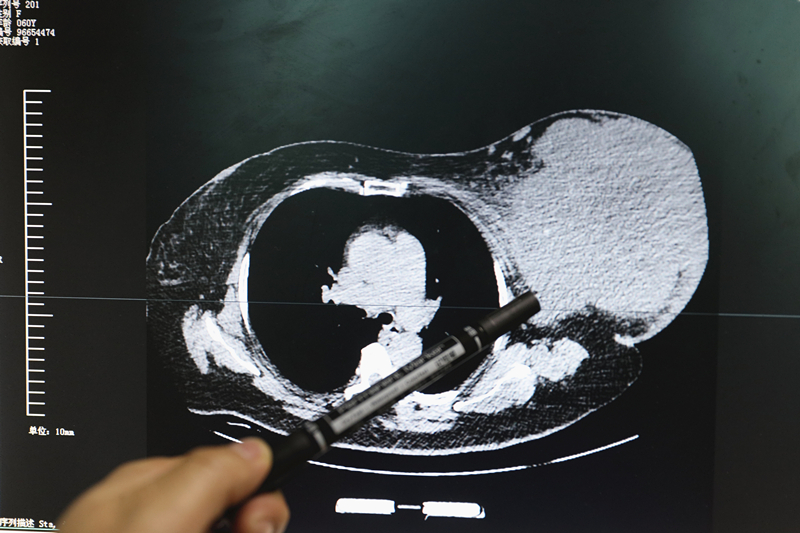

早在5年前,李女士无意中发现自己左侧乳房里长了一个花生大小的肿物,当时也没有痛疼、乳头溢液等不适现象。1年过后,肿物开始有所长大,她便四处寻求偏方进行治疗,但效果一直不是很理想。近半年来,肿物的生长速度明显加快,并且影响到了李女士的日常生活,烟台山医院乳腺外科副主任巩立国表示,“经检查,患者乳房肿物的大小约为30cm*25cm*12cm。巨大肿物给她带来很多不便,胸部长期受其压迫,出现了胸闷、憋气等症状,走路时也不得不弯腰行走,晚上睡觉时也极为不便。她还是一名游泳爱好者,这也影响到了她的游泳锻炼。”

前几日,李女士来到烟台山医院乳腺外科就诊,根据患者病史及辅助检查,专家诊断她可能患上了恶性乳腺叶状肿瘤。乳腺叶状肿瘤(phyllode tumor of the breast,PTB)是发生于女性的一种罕见疾病,发生率约占乳腺肿瘤的0.3% —0.9%,占纤维上皮性肿瘤的2%—3%,手术治疗为最主要的治疗手段。2月14日,在乳腺外科郝经光主任的指导下,巩立国副主任医师、臧红艳主治医师为患者共同手术,巩立国说,“由于肿瘤周围的血供丰富,手术过程中出血量大,有多处血管需要结扎、止血,再加之肿瘤体积巨大,所以这台手术耗时会相对多一些,整个手术历约一个半小时,手术效果非常理想。”